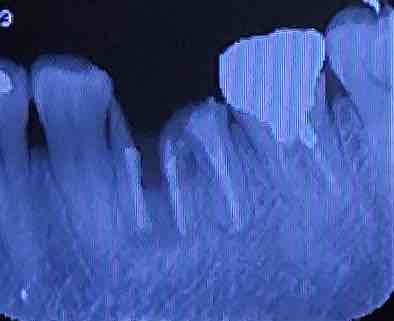

画像添付いたします

画像1CT.JPG 画像2レントゲン.JPG

近親根は真っ二つに割れていて炎症がかなりあるように見えていますが、5年間この根に何かを被せて使用されて来られたのでしょうか?現状の想像が難しいため回答が付き難かったのではないかと想像しました。

せっかくCT撮影もしていただいているようなのに、側方のからの画像しかアップされていないようですが、そもそも、歯根の垂直破折が確認された場合には、骨の温存を鑑み、速やかに抜歯するのが基本なのに、5年も放置してしまったとなると、「 ほんのわずかに骨吸収がはじまりつつある 」 どころか、少なくとも抜歯した時点では、頬側の骨がごっそりなくなっていることが、容易に想像されます。